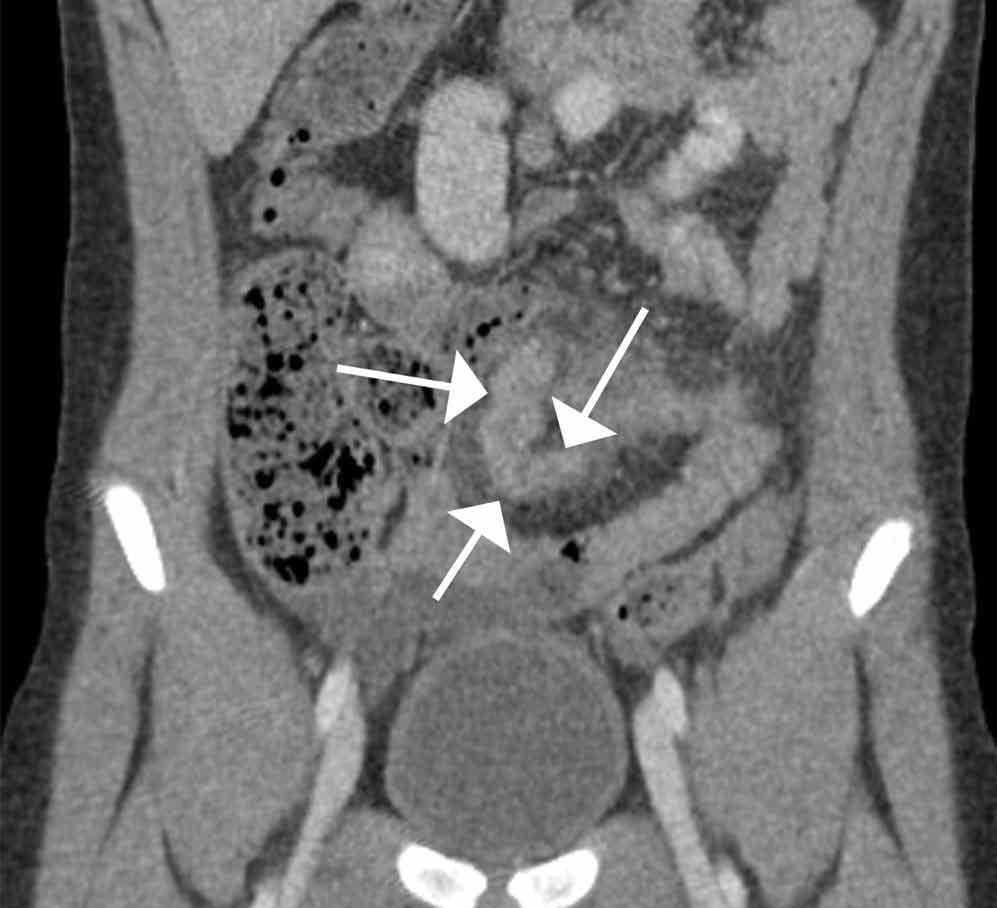

Computed tomography revealed a blind-ending tubular structure (white arrows, Figure 1c) deep to the umbilicus arising inferiorly from a loop of distal ileum with surrounding fat stranding (Figure 1d). The fluid-containing tubular structure demonstrates marked enhancement of the mucosa. These findings are most consistent with Meckel’s diverticulitis.

Figure 1C | Figure 1D |